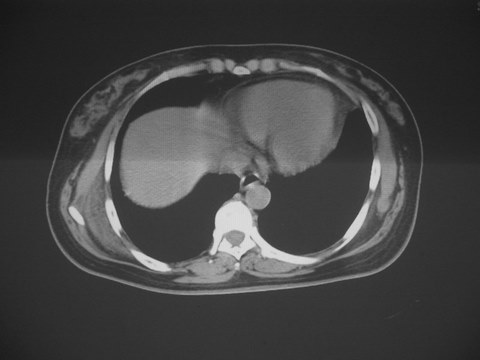

无意中发现右背部肩胛下缘半球状突起,无红,热,痛感觉。拍平片未见异常。ct发现右肩胛下角深层新月型软组织肿胀,ct值-50至15,大家看看是什么性质,来源,初步考虑来源于下后锯肿,考虑下后锯肌肿胀,可是病人无明确外伤史,也不疼痛

典型位于背部,在肩胛下角和胸壁软组织之间,肿瘤表面为菱形肌和背阔肌所被覆深部,紧邻肋骨和肋间肌,呈半圆形或扁豆状,宽基底与胸壁相交,边界比较清楚,相邻的肌肉和肋骨无侵蚀,部分病变与其表面的临近肌肉之间可受压呈弧形的脂肪界面,肿瘤周围软组织无水肿。

从mr表现可以推断ct影像,即肿块呈软组织密度,病灶内可出现脂肪密度的低密度影。

大家注意下 这个病人有乳腺增生,和肩胛下病变没什么关系,但ct下发现乳腺增生的好象不多,因为她有乳腺增生病史,所以才有所注意